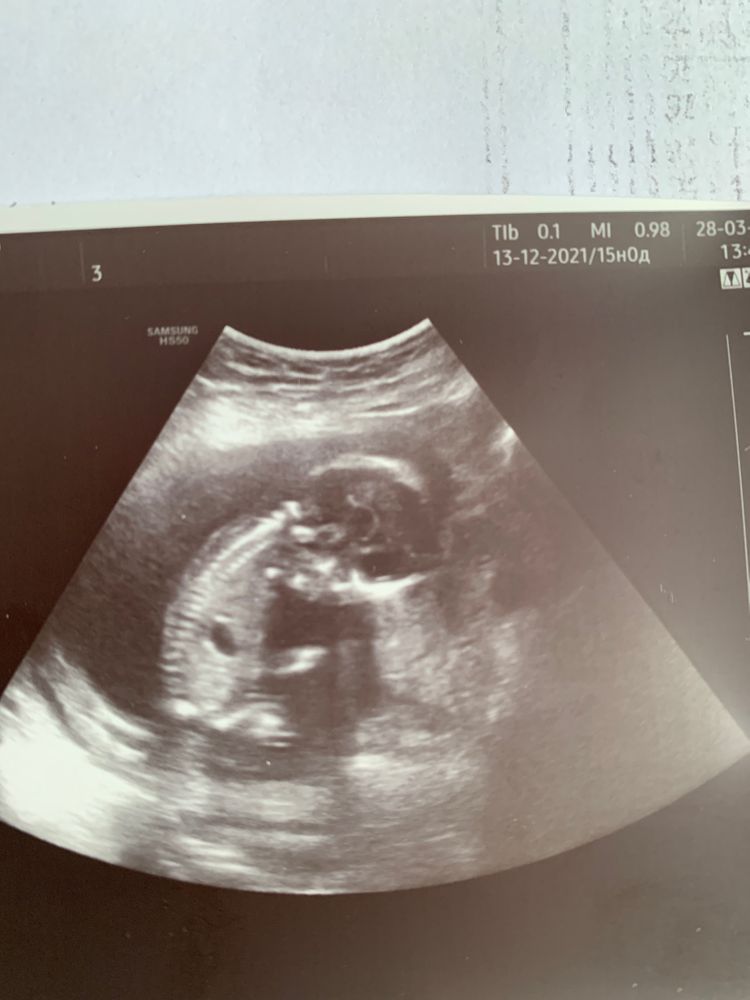

Всем привет! У меня ещё один не очень информативный снимок 🙈 сегодня ровно 15 недель. Узи было другого органа, малыша глянули на минутку , ножки опять скрестил и все спрятал. Снимок только такой. Может кто-нибудь сможет предположить кто же там прячется? После двух мальчиков сгораю от любопытства кто же третий, на второй скрининг через недели три только

Вот так по-турецки сидит больше месяца😀